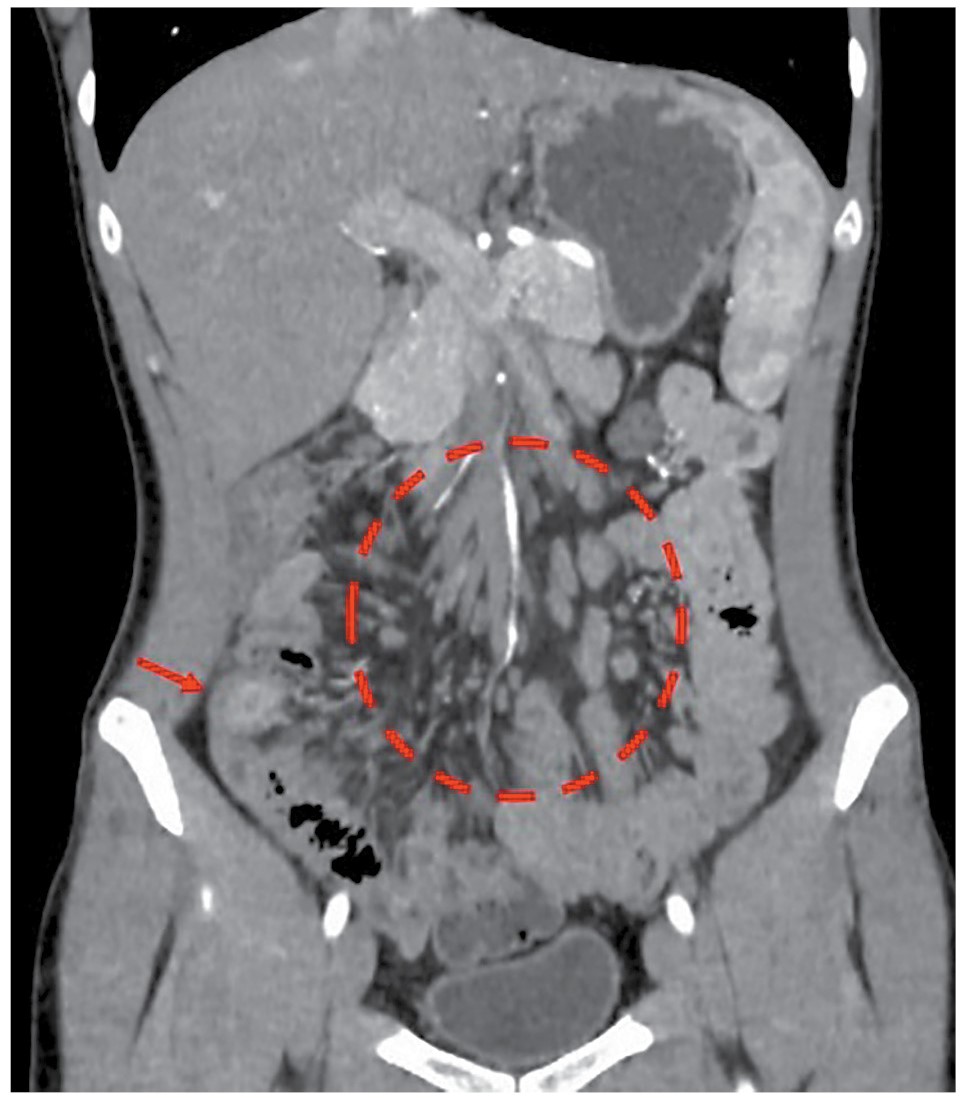

Позже, 05.05.2023, проведено исследование ОГК: по сравнению с исследованием от 09.12.2021 отмечено рассасывание очагово-инфильтративных изменений в СVI правого легкого, формирование туберкуломы до 17 мм в диаметре на фоне грубого фиброза. Продолжена противотуберкулезная терапия, и к 28.08.2023 по заключению фтизиатра у пациента достигнуто клиническое излечение ТБ легких с исходом в фиброз, кальцинаты и крупный очаг (мелкая туберкулома 17 мм) в СVI правого легкого (рис. 1). Рекомендованы хирургическое лечение туберкуломы после закрытия илеостомы и диспансерное наблюдение в противотуберкулезном диспансере по месту жительства в течение 3 лет.

Рис. 1. КТ ОГК больного Л. до (a) и после (b) противотуберкулезной терапии.

Fig. 1. Computed tomography of the chest organs of patient L. before (a) and after (b) anti-tuberculosis therapy.